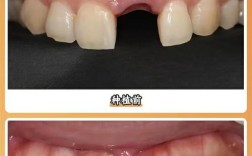

(图片来源网络,侵删)